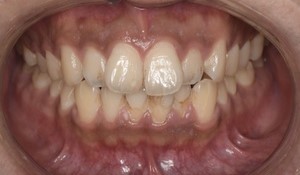

Before

After

基本情報

| 主訴 | 見た目をきれいにしたい |

| 治療期間 | 6ヶ月 |

| 治療費 | ジルコニアボンド(セラミックの被せもの)¥165,000×7(税込み) オフィスホワイトニング4回 ¥4,400×4(税込み) ホームホワイトニング¥11,000 |

| リスク・副作用 | かみ合わせがとても強い方の場合、稀に割れてしまうことがあります。 |

| 先生からの提案 | 上の前歯6本と右下の2番目の歯はセラミックの被せもので治療。 残りの下の前歯5本はプラスチックの材料で虫歯を治療し、 ホワイトニングをおこないました。白くなったご自身の歯の色に合わせてセラミックの 被せものを作成しています。 模型上で完成後をシュミレーションし、上の歯茎の位置をきれいに見えるように 揃えています。(外科処置はしていません) |